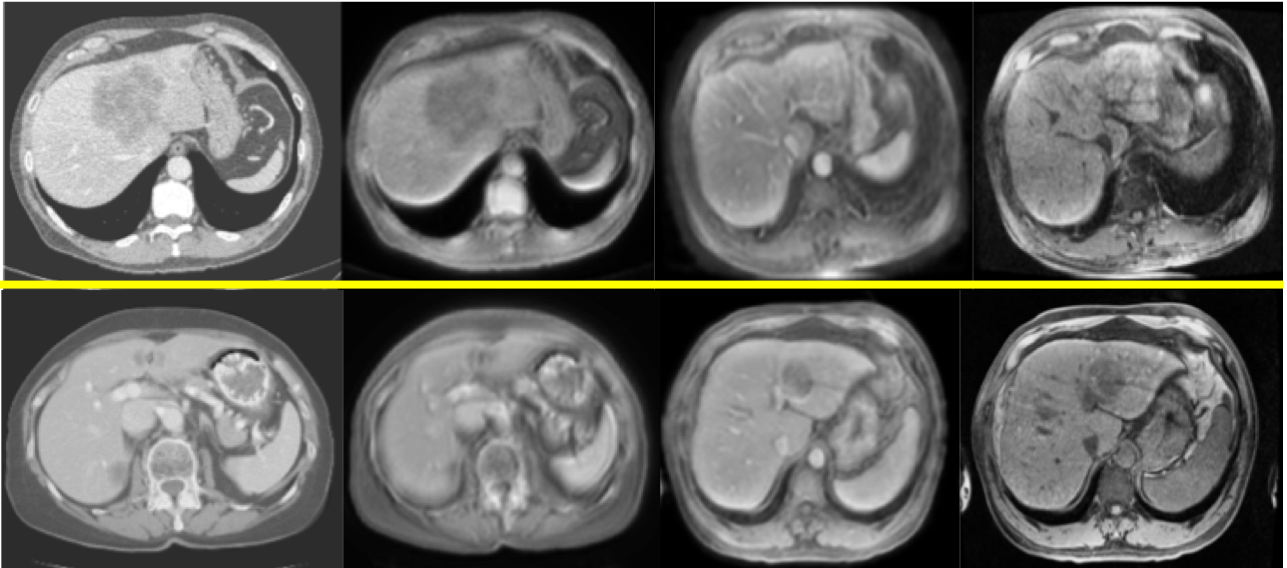

3.2.7 B. Diverse Style Transfer

Furthermore, our model can realize diverse style transfer by changing the style code while preserving the anatomical structure with the same content code. The style code can be randomly sampled in the style space or encoded from a reference image by style encoder Esisubscript𝐸subscript𝑠𝑖E_{s_{i}} (see Fig.  7).

Refer to caption

Figure 7: Three examples of multi-modal style generation with reference, from left to right: CT, three pairs of reference MR and generated MR (pre-contrast, arterial, portal venous phase)